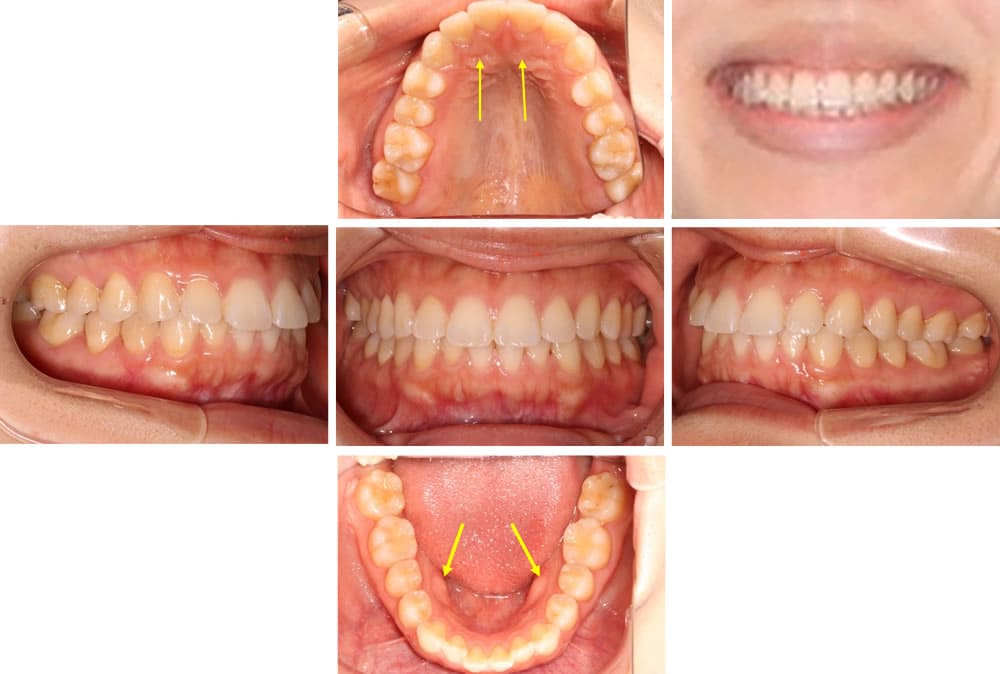

口腔内写真

現象として

- 骨隆起

- ディープバイト傾向

模型による分析

【問題点】

- アーチ狭窄

- 上顎平面左右差

- 後方回転

問題点 (Problem list)

・「歯列で作られるアーチが狭いです」